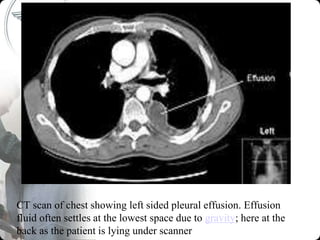

CT scan of chest showing left sided pleural effusion. Effusion

fluid often settles at the lowest space due to gravity; here at the

back as the patient is lying under scanner